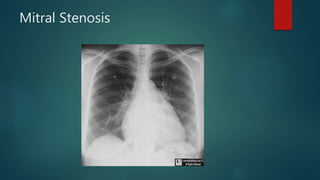

Mitral Stenosis